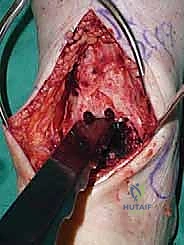

3. إزالة النتوءات العظمية وتحضير المفصل (Debridement)

بمجرد كشف المفصل، يقوم الجراح بإزالة الغشاء الزلالي الملتهب والزوائد العظمية (Osteophytes) التي تعيق الحركة. هذه الخطوة ضرورية لاستعادة المعالم التشريحية الطبيعية قبل إجراء القطع العظمي.

4. وضع أدلة القطع (Jig Placement and Alignment)

تعتمد دقة الجراحة على المحاذاة الصحيحة. يتم استخدام أجهزة توجيه متطورة (Jigs) تثبت على عظمة الساق باستخدام دبابيس معدنية. يتم التحقق من صحة الزوايا والمحاور باستخدام جهاز الأشعة السينية المباشر داخل غرفة العمليات (C-arm Fluoroscopy). يضمن الدكتور هطيف أن يكون القطع موازياً للأرض تماماً عند وقوف المريض.

6. القطع العظمي الكاحلي (Talar Bone Cut)

بشكل مشابه، يتم توجيه دليل القطع نحو عظمة الكاحل (Talus) وإزالة السطح الغضروفي التالف وت